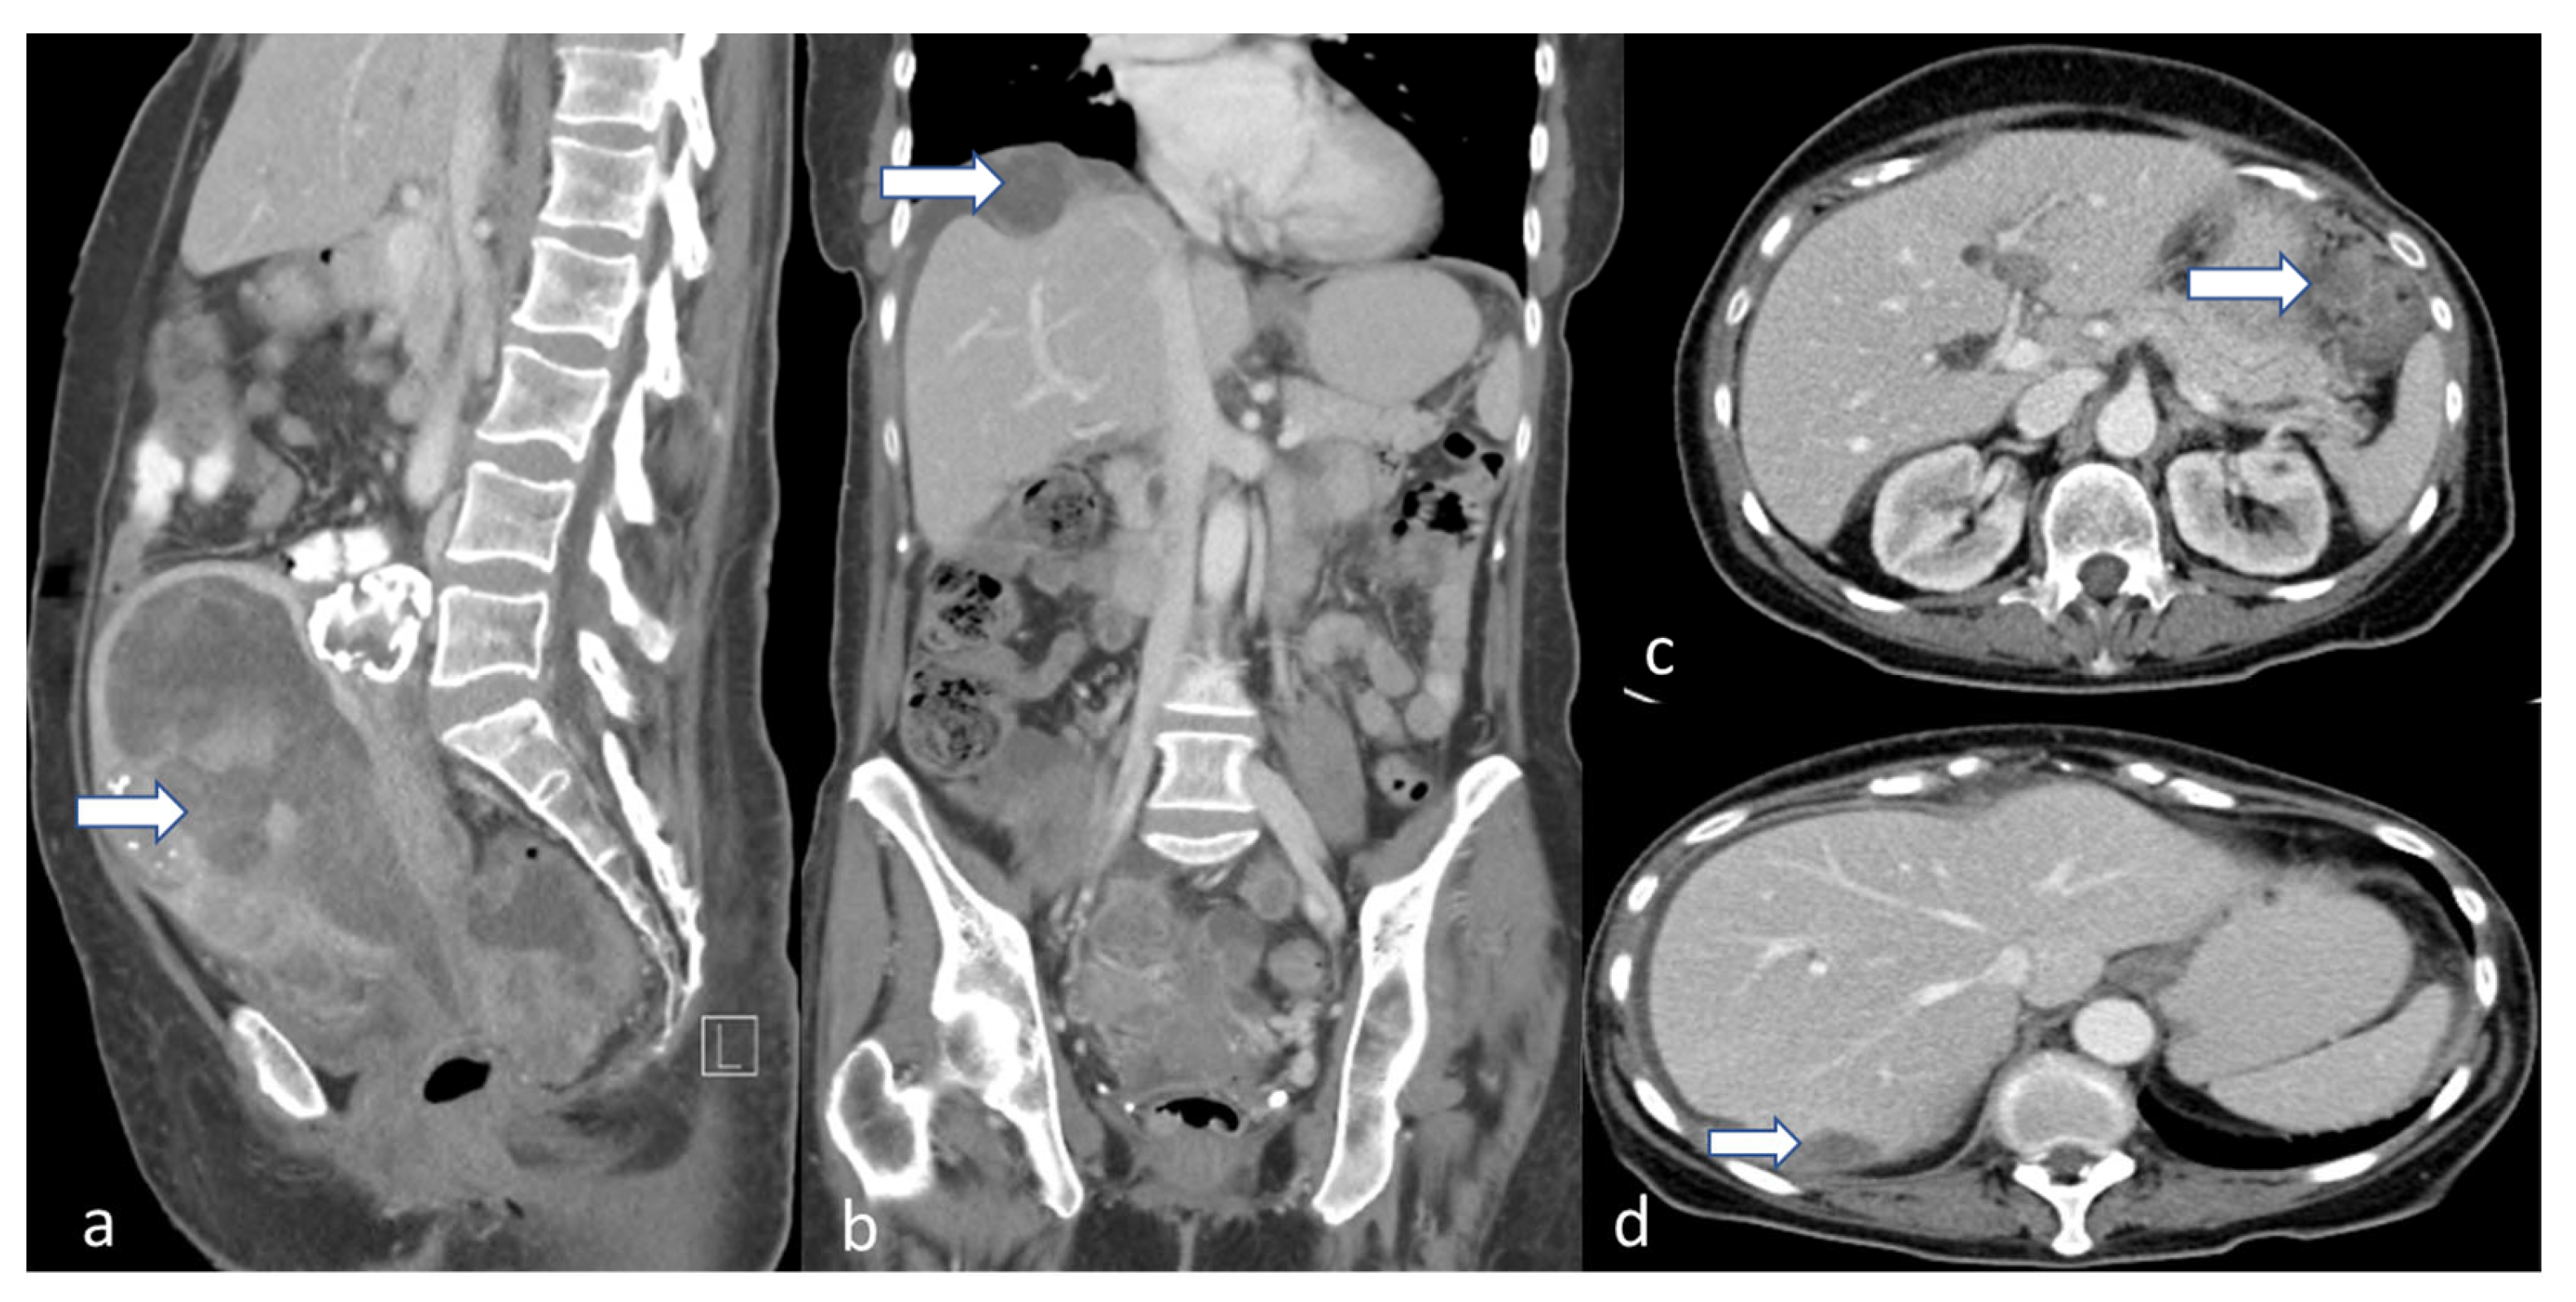

5.2. Computed Tomography (CT)

- Faria, S.C.; Devine, C.E.; Rao, B.; Sagebiel, T.; Bhosale, P. Imaging and Staging of Endometrial Cancer. Semin. Ultrasound CT MRI 2019, 40, 287–294. [Google Scholar] [CrossRef]

- Daoud, T.; Sardana, S.; Stanietzky, N.; Klekers, A.R.; Bhosale, P.; Morani, A.C. Recent Imaging Updates and Advances in Gynecologic Malignancies. Cancers 2022, 14, 5528. [Google Scholar] [CrossRef]

- Saleh, M.; Virarkar, M.; Bhosale, P.; El Sherif, S.; Javadi, S.; Faria, S.C. Endometrial Cancer, the Current International Federation of Gynecology and Obstetrics Staging System, and the Role of Imaging. J. Comput. Assist. Tomogr. 2020, 44, 714–729. [Google Scholar] [CrossRef]

- Faria, S.C.; Sagebiel, T.; Balachandran, A.; Devine, C.; Lal, C.; Bhosale, P.R. Imaging in endometrial carcinoma. Indian. J. Radiol. Imaging 2015, 25, 137–147. [Google Scholar] [CrossRef] [PubMed]